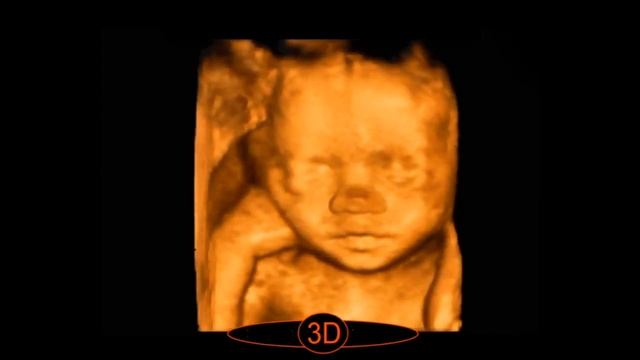

Дорогие будущие родители! Наверняка каждый из вас мечтает увидеть своего будущего ребёнка и сохранить воспоминания об этих чудесных мгновениях. В наше медицинском центре "Профмедклиник" вы можете сделать 3Д/4Д УЗИ. 👉Чем оно отличается от обычного? Обычное УЗИ показывает плоскую чёрно-белую картинку. В 3Д/4Д УЗИ вы можете увидеть объемное движущиеся изображение ребёнка, а так же получить фото или видеозапись. 3Д/4Д УЗИ ✅Вы сможете посмотреть черты лица будущего ребёнка ✅Увидеть мимику и движения ребёнка ✅Уточнить пол ребёнка ✅Убедиться в отсутствии патологий ✅Получить фото и видео запись ✅При желании посетить УЗИ со своими близкими Телефон для записи: 8(4012) 30-02-45 Медицинский центр "Профмедклиник" @profmedclinic